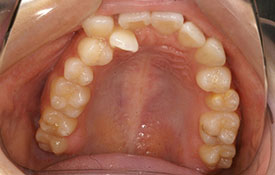

| プロフィール | 15歳 男性 |

| 所見 | アメリカから転院されて来られた方です。 インビザラインで上下顎の矯正治療を開始し下顎はアメリカで終了しており、上顎のみ治療の後期を担当しました。 アイライナーの装着は、1日平均22時間ほどでした。 |